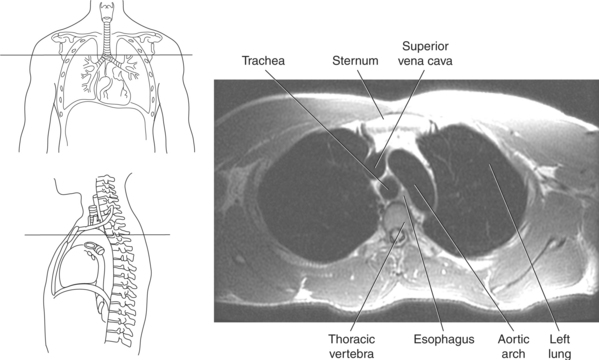

The mediastinum is the midline region of the thoracic cavity located between the two pleural cavities of the lungs. It extends from the superior thoracic aperture to the diaphragm and is bordered anteriorly by the sternum and posteriorly by thoracic vertebrae. The mediastinum can be subdivided into compartments for descriptive purposes. The superior and inferior compartments are made by drawing an imaginary line between the sternal angle and the intervertebral disk of T4-T5. The superior compartment constitutes the upper portion of the mediastinum. It contains the thymus gland and acts as a conduit for structures as they enter and leave the thoracic cavity. The inferior compartment can be further divided into anterior, middle, and posterior compartments (Figure 6.23). The anterior compartment is located anterior to the pericardial sac and posterior to the sternum. The middle compartment is the area that contains the pericardial sac, heart, and roots of the great vessels. The posterior compartment is the area lying posterior to the pericardium and anterior to the inferior eight thoracic vertebrae. Structures located within the mediastinum include the thymus gland, trachea, esophagus, lymph nodes, thoracic duct, heart and great vessels, and various nerves.

Throughout its course in the mediastinum, the trachea runs anterior to the esophagus. In cross section, the trachea appears as a round air-filled structure to the point at which it bifurcates at the carina (Figures 6.9 and 6.18). The esophagus appears as an oval-shaped structure that descends through the diaphragm to enter the stomach at the gastroesophageal junction (Figures 6.27 and 6.28).

Blood travels to and from the heart through the great vessels, which include the aorta, pulmonary arteries and veins, and superior and inferior venae cavae (Figures 6.54 and 6.55). The aorta is the largest artery of the body and can be divided into the ascending aorta, aortic arch, and descending aorta. The ascending aorta begins at the base of the left ventricle at the level of the sternal angle, then curves superiorly and posteriorly as the aortic arch over the root of the left lung. The top of the aortic arch is approximately at T3 (Figures 6.56 and 6.57). The arch continues as the descending aorta posterior to the left bronchus and pulmonary trunk, on the left side of the vertebral body of T4 (Figures 6.58 and 6.59). The descending aorta passes slightly anterior and to the left of the vertebral column as it descends through the thoracic and abdominal cavities (Figure 6.60). While in the thoracic cavity, the descending aorta is commonly called the thoracic aorta, and while in the abdominal cavity, it is called the abdominal aorta. The pulmonary trunk is the origin of the right and left pulmonary arteries and lies entirely within the pericardial sac. It arises from the right ventricle and ascends in front of the ascending aorta, courses posteriorly and to the left, where it bifurcates at the level of the sternal angle (T4) into the right and left pulmonary arteries (Figures 6.61 through 6.63). The pulmonary trunk is attached to the aortic arch by a fibrous cord called the ligamentum arteriosum, the remnant of an important fetal blood vessel (ductus arteriosus) that links the pulmonary and systemic circuits during fetal development (Figures 6.54 and 6.61). The right pulmonary artery courses laterally, posterior to the ascending aorta and superior vena cava, and anterior to the esophagus and right mainstem bronchus, to the hilum of the right lung. At the root of the right lung, the right pulmonary artery divides into two branches, with the lower branch supplying the middle and inferior lobes and the upper branch supplying the superior lobe (Figures 6.61 through 6.64). The left pulmonary artery, shorter and smaller than the right, is also the most superior of the pulmonary vessels. It travels horizontally, arching over the left mainstem bronchus, and enters the hilum of the left lung just superior to the left mainstem bronchus (Figures 6.61 through 6.64). Within the lungs, each pulmonary artery descends posterolateral to the main bronchus and divides into lobar and segmental arteries, continuing to branch out and to follow along with the smallest divisions of the bronchial tree (Figures 6.61 and 6.64). Located inferior to the pulmonary arteries are the four pulmonary veins, two each (superior and inferior) extending from each lung to enter the left atrium (Figures 6.54, 6.55, 6.61, and 6.64 through 6.68). They commence in a capillary network along the walls of the alveoli, where they are continuous with the capillaries of the pulmonary arteries. The venous capillaries merge to form small vessels that unite successively to eventually form a single trunk for each lobe: three for the right and two for the left lung. Frequently the trunk from the middle lobe of the right lung unites with the trunk from the upper lobe, forming just two trunks on the right side prior to entering the left atrium. The right superior pulmonary vein collects blood from the upper lobe segments of the right lung and passes anterior and inferior to the right pulmonary artery, behind the superior vena cava. The right inferior pulmonary vein receives blood from the right lower lobes of the lung and crosses behind the right atrium to the left atrium (Figures 6.61 and 6.69 through 6.71). The left superior pulmonary vein receives blood from the left upper lobe of the left lung and courses anterior and inferior to the left main bronchus as it enters the left atrium. The left inferior pulmonary vein drains the inferior lobe of the left lung and passes toward the left atrium anterior to the bronchi (Figures 6.61 and 6.72 through 6.74). The pulmonary veins course more horizontally than the pulmonary arteries and are ultimately oriented toward the left atrium. At the root of the lungs, the pulmonary veins are anterior to the pulmonary arteries, which are anterior to the bronchus. While within the lungs, the branches of the pulmonary arteries are anterior to the bronchi, which are anterior to the pulmonary veins. The superior and inferior venae cavae are the largest veins of the body. The superior vena cava is formed by the junction of the brachiocephalic veins, posterior to the right first costal cartilage, and carries blood from the thorax, upper limbs, head, and neck (Figure 6.24). As it travels inferiorly, it is located posterior and lateral to the ascending aorta before entering the upper portion of the right atrium (Figures 6.54 through 6.59). The inferior vena cava is formed by the junction of the common iliac veins in the pelvis and ascends the abdomen to the right of the abdominal aorta and anterior to the vertebral column. It passes through the caval hiatus of the diaphragm and almost immediately enters the inferior portion of the right atrium (Figures 6.75 and 6.76).